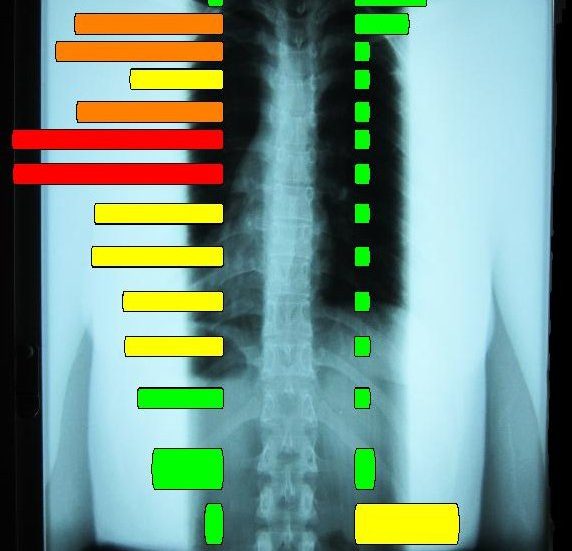

The Titron Thermography Scanners read the temperature bilaterally simultaneously to gather the data on the paraspinal temperature radiated from these capillary beds. The graphs produced by the scan show the temperature of the scanned anatomy, and with some math, show the balance of the temperatures graphed at that time. Coupled and layered with other graphs from other days and before- and after-visit scans, if patterns of non-adaptation appear, it would indicate an abnormal control system and possible dysautonomia.

The regular use of paraspinal thermography, and the study of the results, would lend great aid to identifying and starting care for someone in the slow slide away from health and vitality into the depths of dysautonomia.